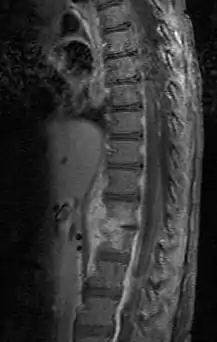

Discitis in a 2 year old child.

Diagnosis is usually apparent on MRI, although plain X-rays and CT examinations can be suggestive. The MRI will reveal air changes in the disc and possibly even external involvement involving the bone or epidural regions. A biopsy may be performed and helps with diagnosis in some cases but often an organism is not obtained. C-reactive protein levels and ESR levels will be elevated and are useful for treatment. Often, the white blood cell count will be normal and the patient will be afebrile.